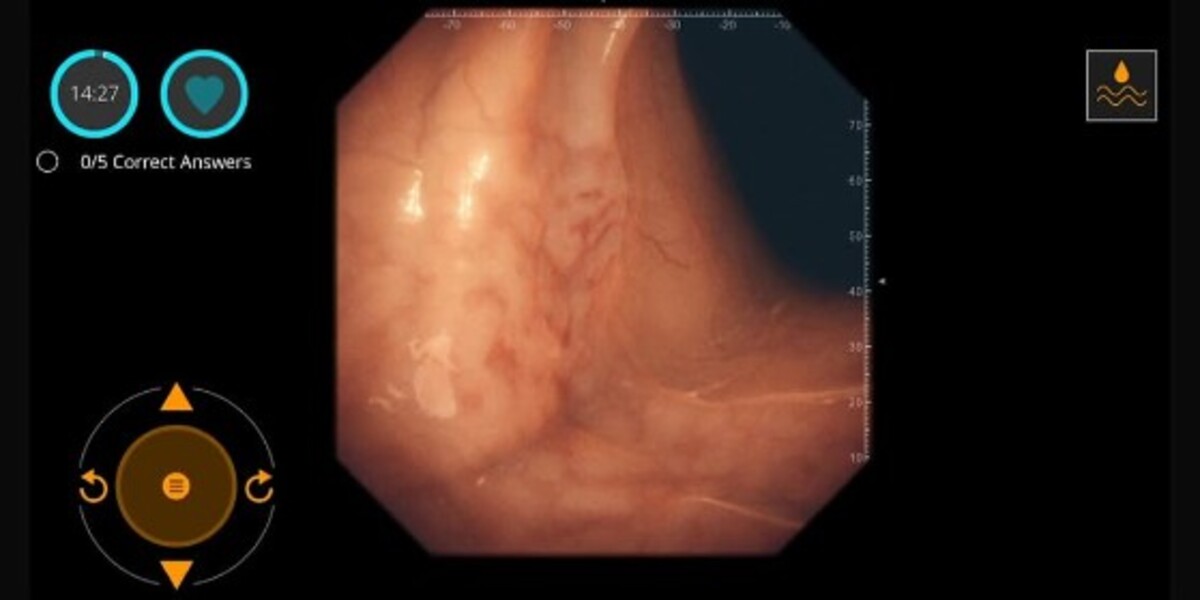

Gastro Ex

เป็นเกมการผ่าตัดที่แม่นยำและเข้มข้นที่สุดที่นี่ โดยเน้นไปที่การทำงานของแพทย์ระบบทางเดินอาหารและดูเหมือนว่าพวกเขาจะใช้เช่นกัน Gastro EX ให้คุณสำรวจความกว้างใหญ่และความซับซ้อนของระบบทางเดินอาหาร ซึ่งเป็นบ่อเกิดของปัญหาในบุคคลทุกประเภท คุณต้องสำรวจแผ่นพับต่างๆ อย่างรอบคอบและรายงานเงื่อนไขใดๆ ที่คุณอาจพบ จากข้อมูลดังกล่าว คุณสามารถตัดสินใจเลือกขั้นตอนที่เหมาะสมเพื่อดำเนินการต่อไปเพื่อทำความสะอาดสุขภาพภายในของผู้ป่วย เพื่อให้พวกเขามีชีวิตภายนอกที่ดีขึ้